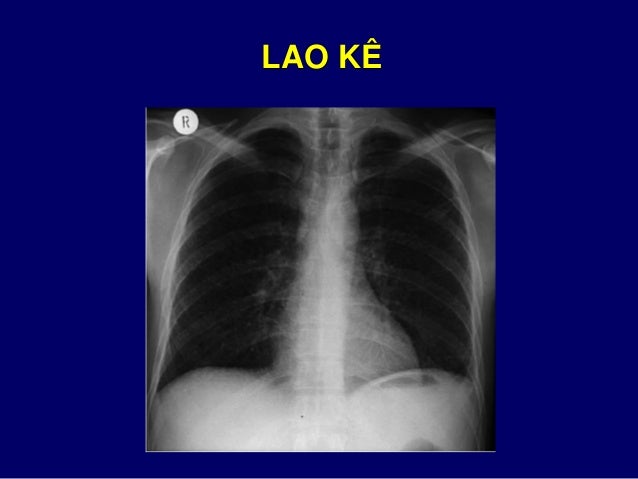

106. 106. 6. CÁC TỔN THƯƠNG KHÁC NHỒI MÁU PHỔI  Dấu hiệu “Hampton hump”  Hình mờ hình tam giác hay hình vòm  Đáy nằm trên màng phổi  Đỉnh nhọn hướng về rốn phổi

107. 107. 5. CÁC TỔN THƯƠNG KHÁC SẠN PHẾ QUẢN

129. 129. TỔN THƯƠNG DẠNG HẠT KÊ NỐT HẠT KÊ

130. 130. LAO KÊ